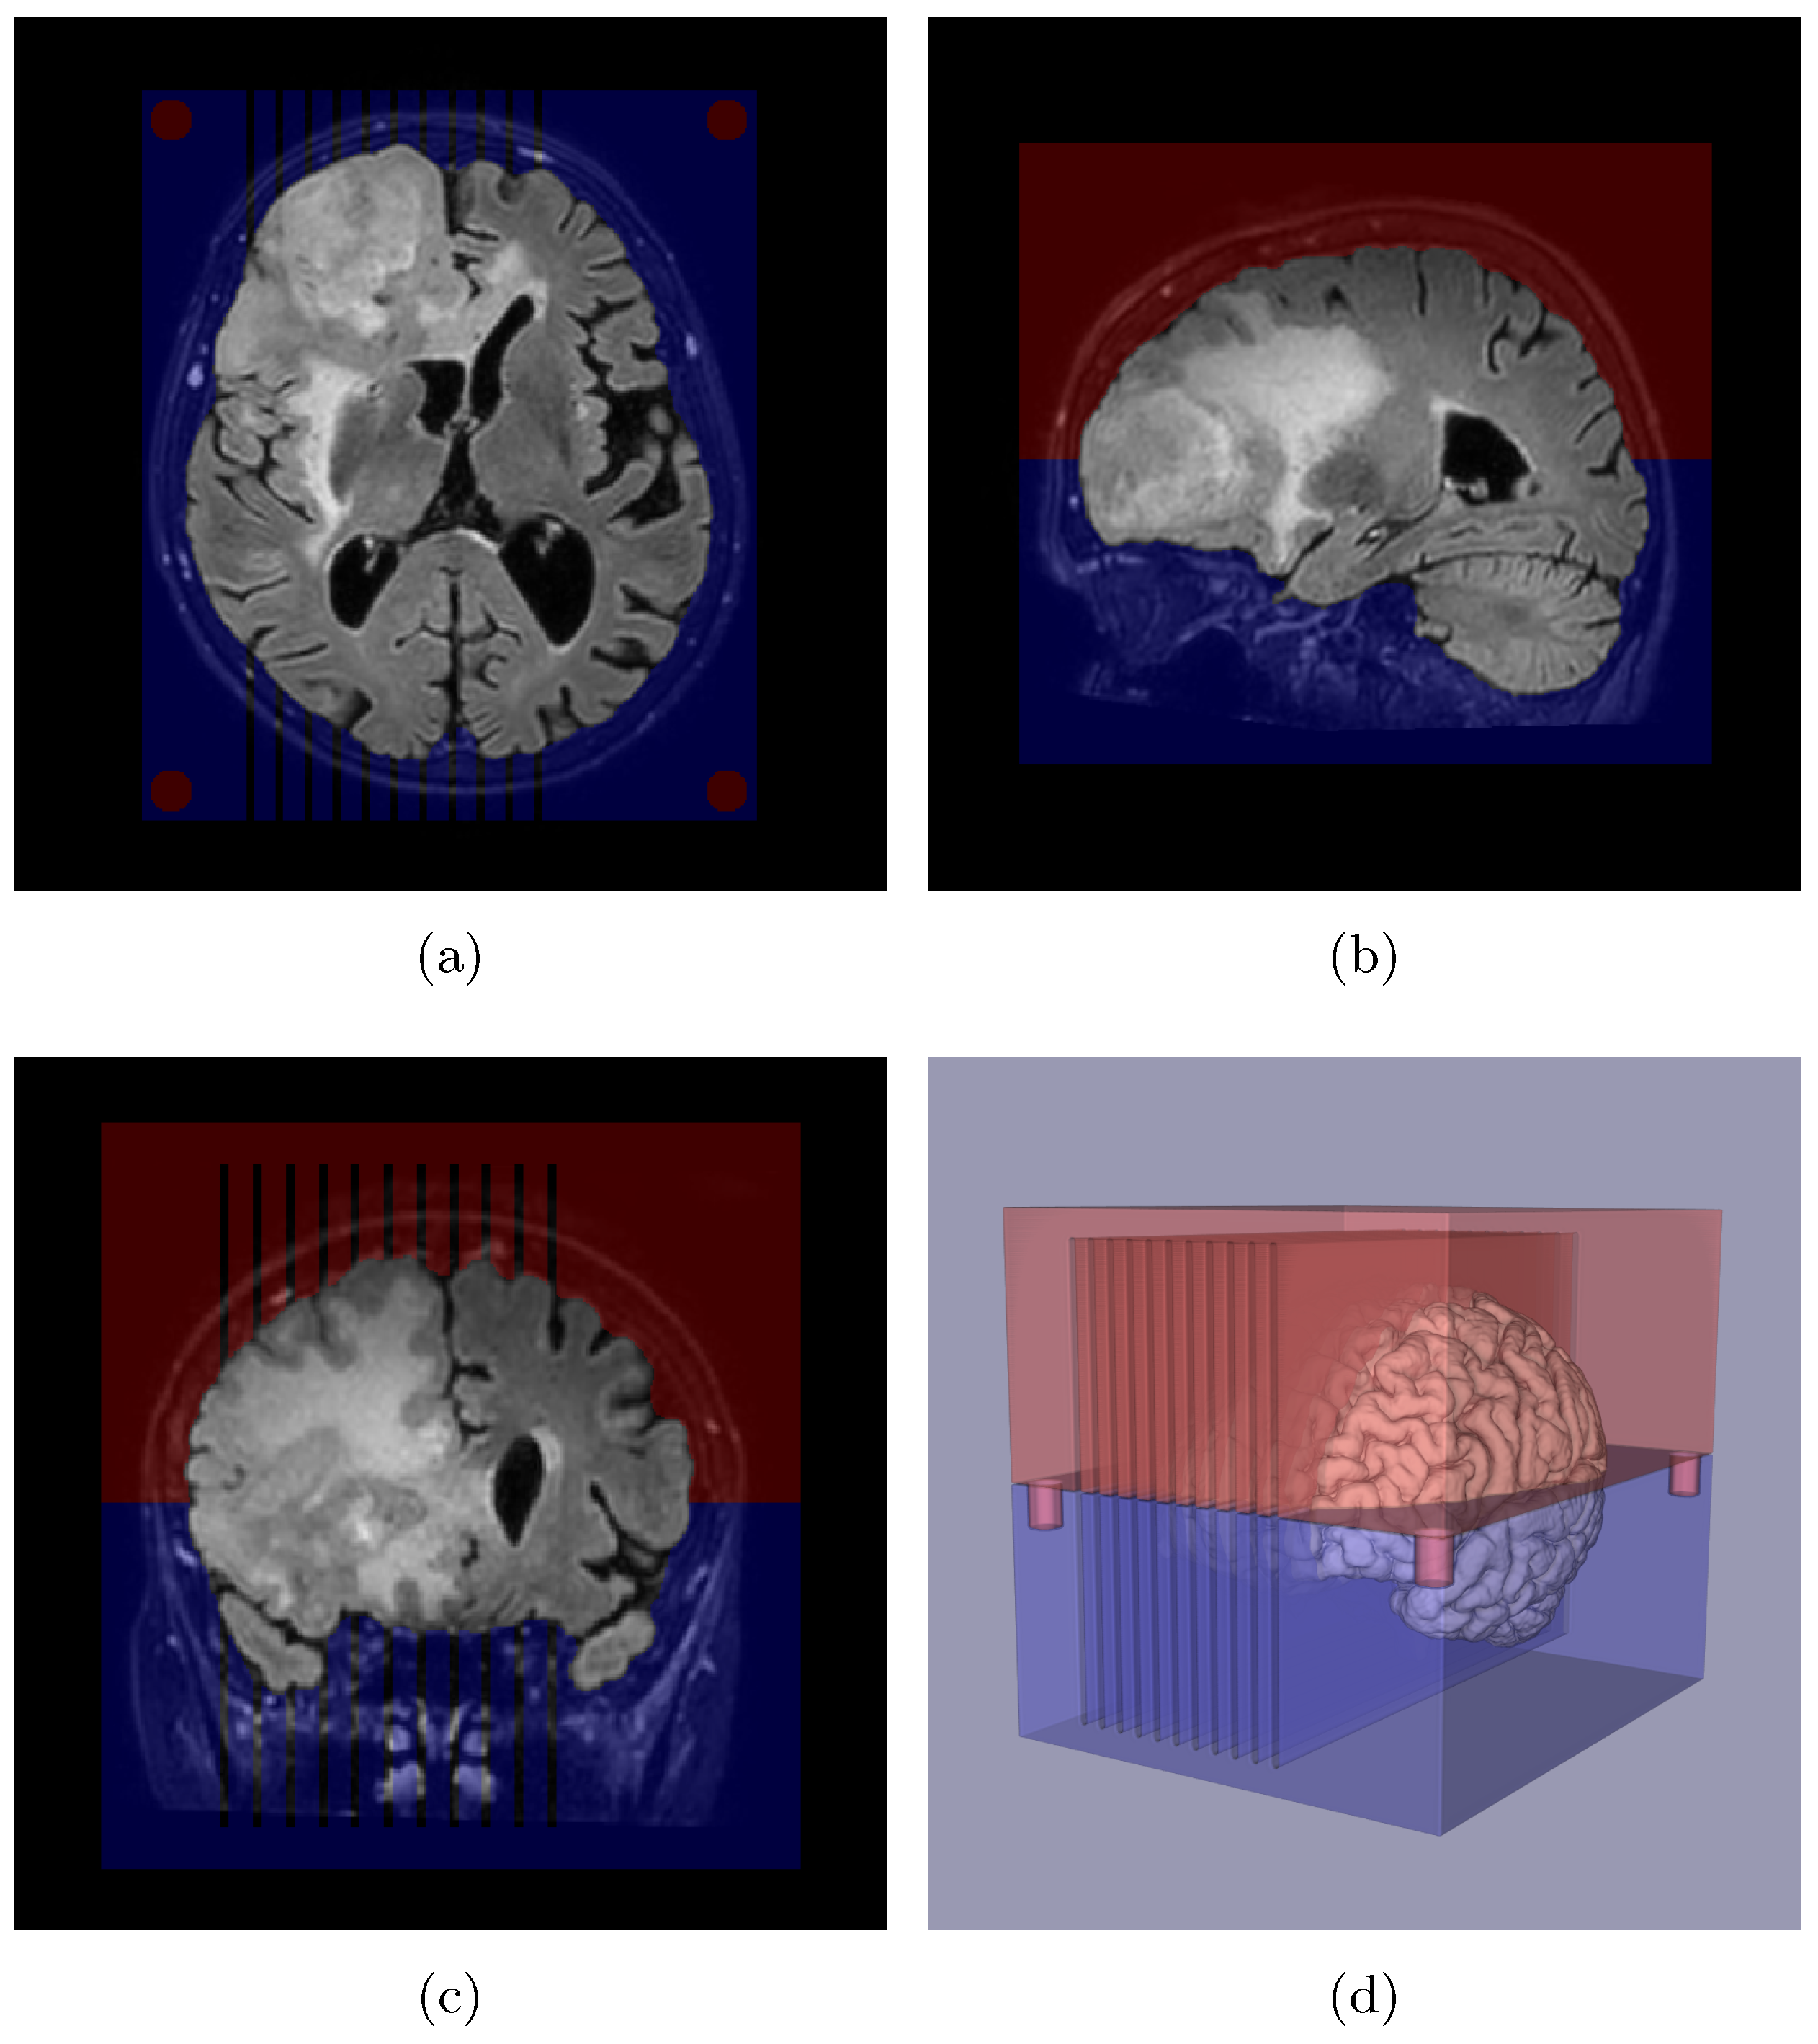

2.3. Slicer Design and Tissue Sampling

Appendix A. Slicer Design